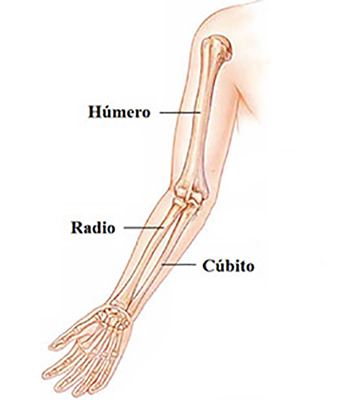

El Húmero (en latín, humerus) es el hueso más largo de las extremidades superiores en el ser humano. Forma parte del esqueleto apendicular superior y está ubicado en la región del brazo. ... El extremo proximal del húmero tiene la cabeza, cuellos quirúrgico y anatómico y tubérculos mayor y menor.

El Húmero (en latín, humerus) es el hueso más largo de las extremidades superiores en el ser humano. Forma parte del esqueleto apendicular superior y está ubicado en la región del brazo. ... El extremo proximal del húmero tiene la cabeza, cuellos quirúrgico y anatómico y tubérculos mayor y menor.